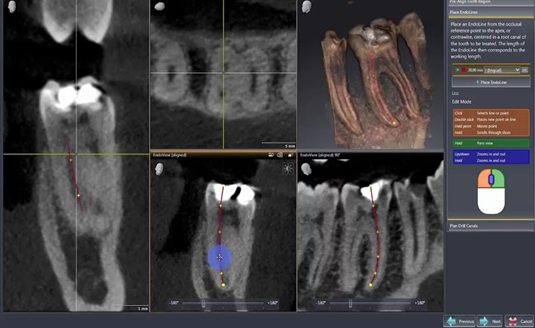

- CBCT trong điều trị nội nha: Trong điều trị tuỷ hay điều trị nội nha, cấu trúc giải phẫu ống tuỷ phức tạp như ống tuỷ chia sâu, ống tuỷ rẽ nhánh, các ống tuỷ phụ, ống tuỷ hình C và các tình trạng bệnh lý tuỷ như sỏi tuỷ, calci hoá ống tuỷ gây khó khăn rất nhiều cho việc điều trị và không thể thấy được trên phim X quang 2D thông thường. Với phim chụp CBCT sẽ hỗ trợ tối đa cho Bác sĩ trong việc đánh giá giải phẫu ống tuỷ theo 3 chiều không gian cũng như phân tích được những cản trở, bệnh lý ống tuỷ hỗ trợ cho điều trị tốt hơn. | | |